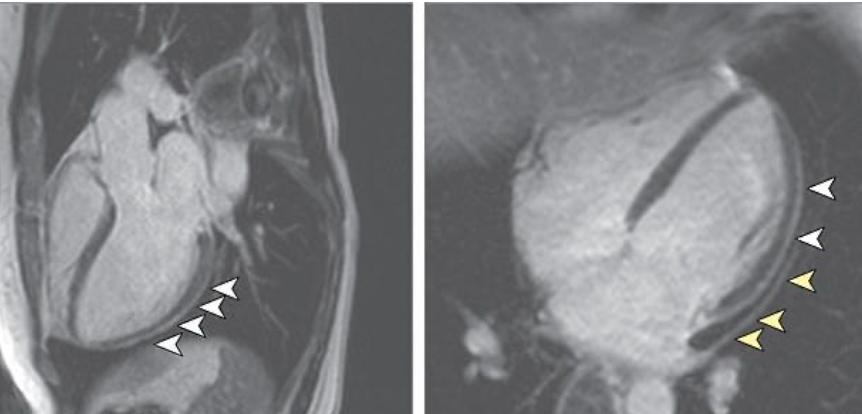

德国法兰克福大学医院的研究人员的第一项研究检测了100名新冠病毒感染者的心脏健康状况。50名研究参与者在感染之前是健康的,另外57名在其他方面(年龄、种族和性别)相似的人有患上心脏疾病的危险。研究人员在其中78人的核磁共振成像中看到心脏损伤的迹象,几乎有76%的人体内肌钙蛋白含量很高,与心脏病发作的人的水平相当。其中60名参与者有心脏炎症的迹象,尽管他们被诊断为新冠病毒后已经过了71天了。